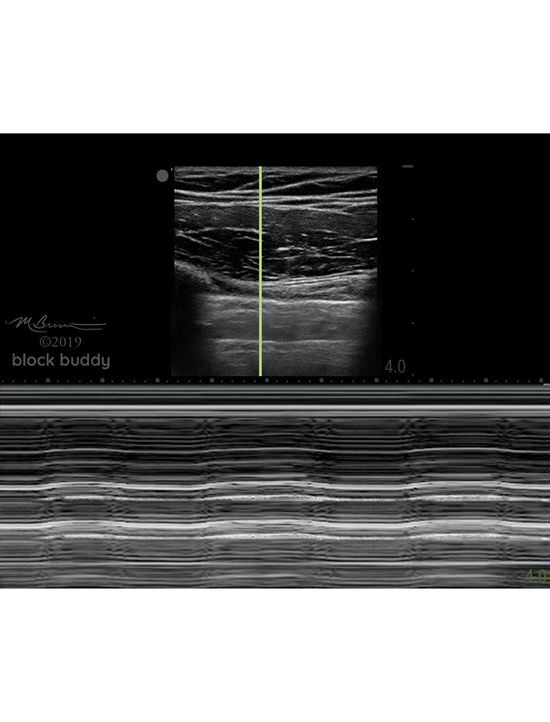

M-mode (motion mode)

- Measures the motion of a structure over a period of time.

- After obtaining a B-mode image, a single scan line (yellow line) is placed over the pleura between the ribs.

- A normal aerated lung will present as the “seashore sign” or “waves on the beach”.

- The “waves” will appear as horizontal, hyperechoic lines.

- Represents the lack of motion in the chest wall.

- The area below the pleural line will appear granular (“beach”)

- Results from the motion of the lung.

- M-mode can be used to measure the motion of the chest wall and lung.

- When a pneumothorax is present, the “bar code” sign will appear as horizontal, hyperechoic lines across the screen.

- Represents the lack of motion in the chest wall and lung.